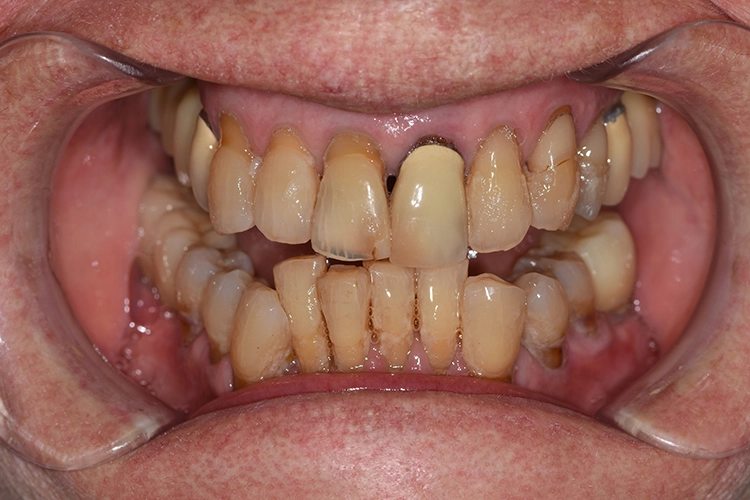

Bei den meisten alltäglichen Tätigkeiten wie Körperpflege und Kochen gaben die 100-Jährigen an, Hilfe zu benötigen. Obwohl offensichtliche Defizite in der häuslichen Mundhygiene vorlagen, wie generalisiert harte und weiche Beläge, schlecht gereinigter herausnehmbarer Zahnersatz, Druckstellen usw., gaben nur 7 (12,7%) der 100-Jährigen an, hierbei Hilfe zu benötigen. Die Abbildungen 1 bis 3 zeigen beispielhaft die klinische intraorale Situation von 3 100-Jährigen, die an der Untersuchung teilgenommen haben.